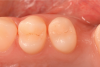

The placement of posterior restorations may lead to postoperative sensitivity.19 Two main characteristics that are important to consider when dealing with posterior restorations are the configuration factor (C-factor) of the preparation and the amount of dentin involved when compared with the amount of enamel. A preparation's C-factor refers to the ratio of bonded to unbonded surfaces. For example, Class I preparations have a C-factor of 5, and Class II preparations have a C-factor of 2. For preparations in which the amount of dentin is greater than the amount of enamel, a self-etch approach is advised because it may reduce postoperative sensitivity. Universal adhesives with functional monomers are able to chemically bond to dentin, which exists in greater amounts in posterior teeth.20 Using them in a selective enamel etching approach can improve the marginal seal that is obtained. In the clinical case described here, two premolars were restored using a universal adhesive in a selective enamel etching approach. The patient presented with primary and a secondary caries on teeth Nos. 12 and 13 (Figure 1). After isolation with a rubber dam (Figure 2), the teeth were prepared using a cylindrical bur, and the enamel was selectively etched with phosphoric acid (Figure 3). A universal adhesive was then applied, and composite was placed to restore the tooth using a cusp-by-cusp modeling approach (Figure 4 and Figure 5).

(1.) Pretreatment photograph of primary and a secondary caries on teeth Nos. 12 and 13.

Figure 1